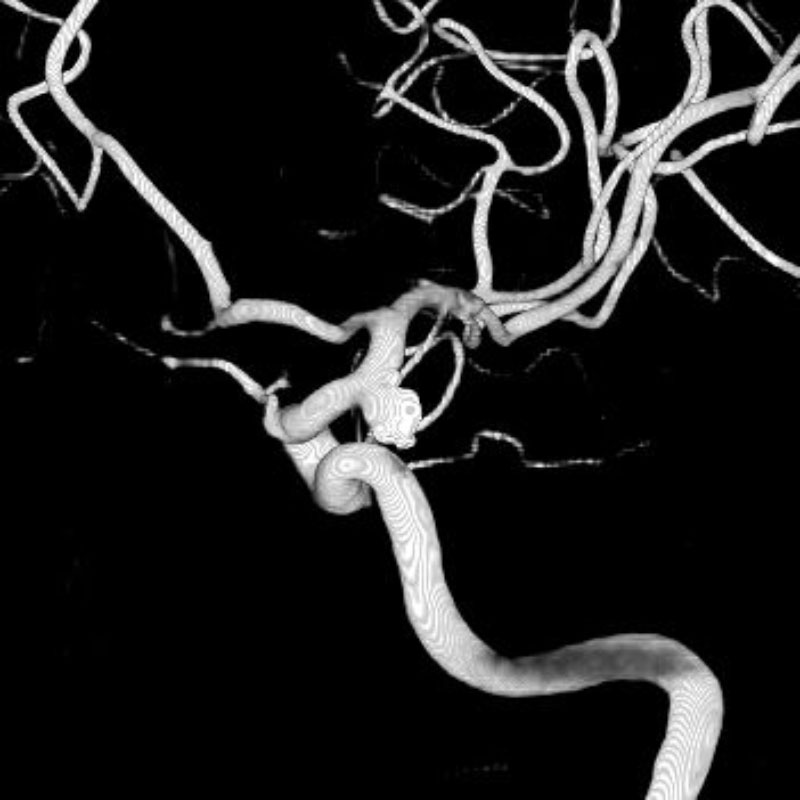

脳動静脈奇形

血管塞栓術

松田/濵田/元永